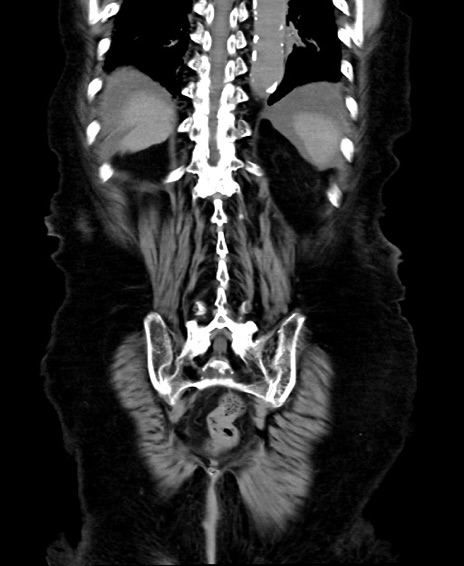

症例40(冠状断像)他院1日前

【症例】90歳代女性

【主訴】腹痛・嘔吐

【現病歴】 食欲低下、嘔吐があり昨日他院受診。肺炎と診断され入院となる。入院後より腹部全体に圧痛あり。胃管留置され経過みていたが、症状持続するため、

当院転院となる。

【既往歴】胸椎圧迫骨折、胆石症

【身体所見】腹部:中央に激痛あり、圧痛あり、反跳痛不明

【データ】WBC 17100、CRP 18.82

冠状断像